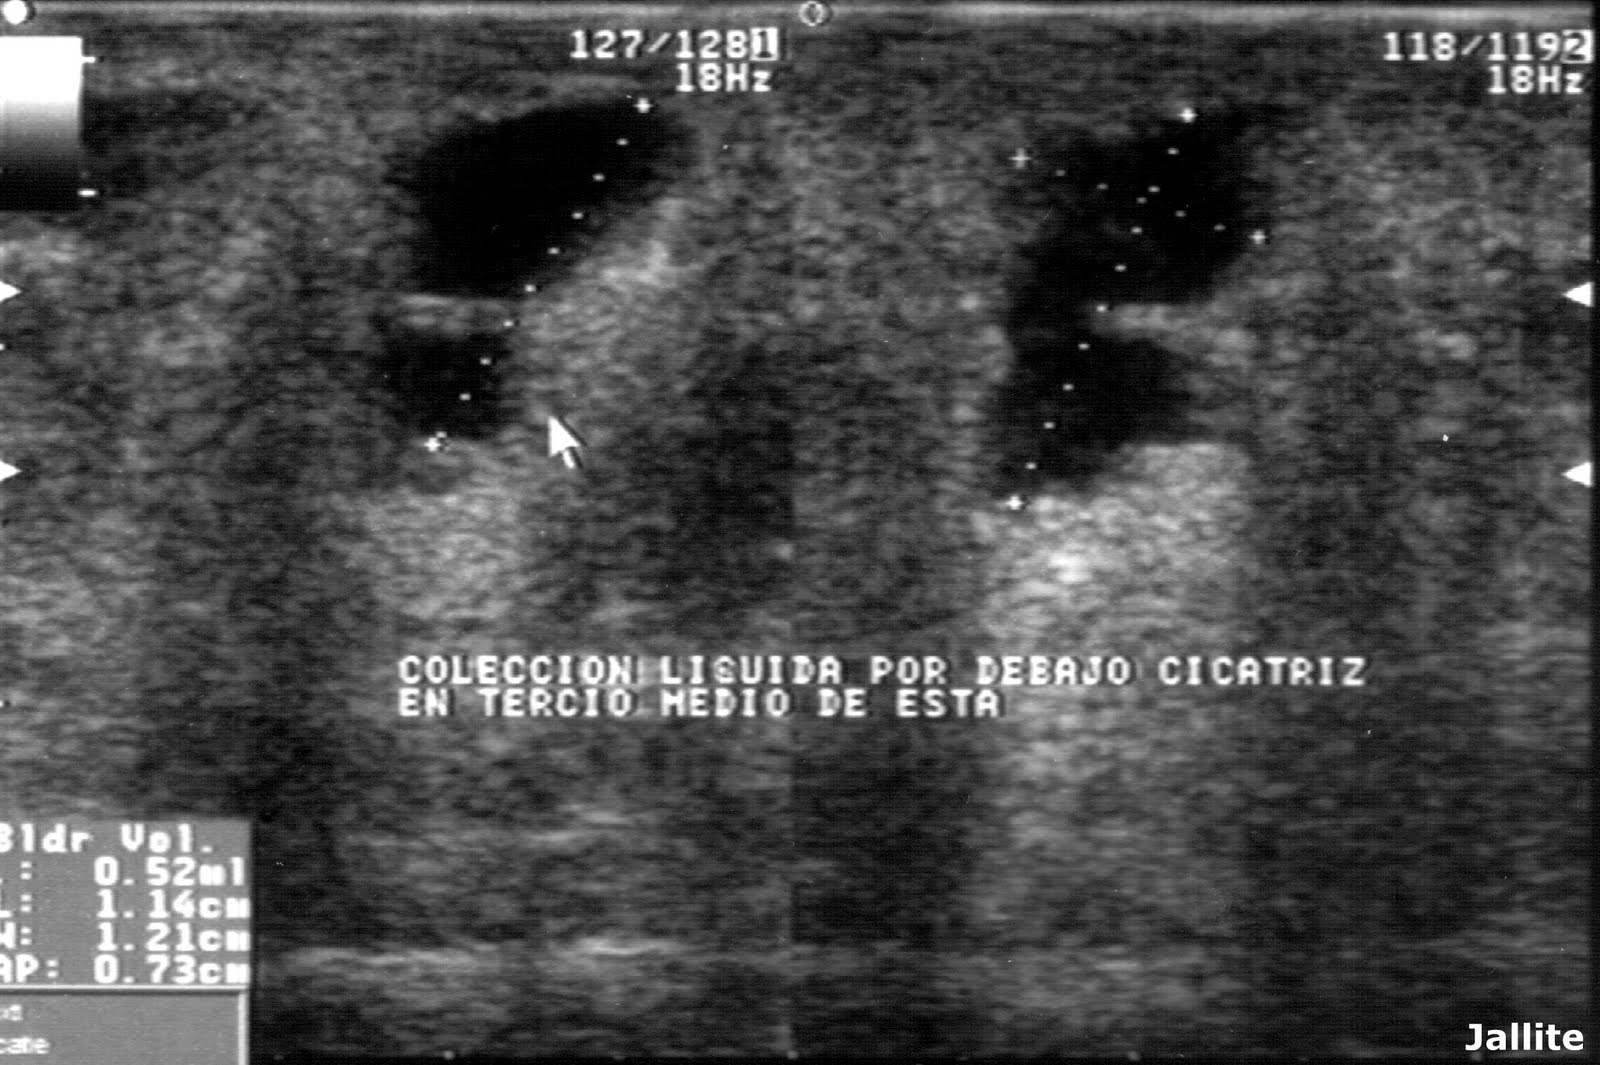

WebComo ya sabes, el seroma es la complicación de una cicatrización en la que hay parte del tejido de la piel que no ha llegado a cerrar bien. Esto ha provocado una bolsa donde se.

WebEl seroma tardío es una complicación que puede darse después de una cirugía plástica. Cuando se reduce la grasa o el volumen de una zona concreta. Por ejemplo, en el caso. WebEl seroma es la acumulación de líquidos corporales transparentes en un lugar del cuerpo de donde se ha extirpado tejido mediante cirugía. WebEl seroma es una posible complicación en intervenciones quirúrgicas como la mamoplastia de aumento. Cuando surgen se forman acumulaciones de líquido. WebHe hecho varias preguntas sobre mi complicación en el pecho izquierdo después de mastopexia. Se creó un seroma enorme que acabó abriendo 3 puntos por la. Web¿Qué es un seroma? El seroma es una acumulación anormal de fluidos serosos. Un líquido seroso es aquel que se parece al suero, de color amarillo pálido y. WebUn seroma es una complicación que puede ocurrir como resultado de la cirugía. Implica la acumulación de líquido en un tejido u órgano. Muy a menudo, se. WebUn seroma es una acumulación de líquido compuesto de grasa, linfa y suero de características inflamatorias (no infeccioso), normalmente claro, de aspecto similar. Web¿Qué es un seroma en el pecho? Un seroma es la acumulación de líquido en un espacio o cavidad que ha sido formada en una intervención quirúrgica. Tras una herida es.

WebEl seroma es una afección médica común que ocurre después de la cirugía en el sitio de la incisión quirúrgica. Ocurre como una respuesta de defensa al trauma. WebSe trata de un rechazo agudo del implante por parte del cuerpo, que lo expulsa, habitualmente debido a un proceso infeccioso. Digamos que, en caso de infección, el. Web¿Qué es el seroma en el pecho? El seroma en el pecho, luego de una cirugía, se forma cuando se acumula un exceso de líquido en la cavidad mamaria, es como una.

WebUn seroma es una acumulación de líquido compuesto de grasa, linfa y suero de características inflamatorias (no infeccioso), normalmente claro, de aspecto similar. Web¿Qué es un seroma en el pecho? Un seroma es la acumulación de líquido en un espacio o cavidad que ha sido formada en una intervención quirúrgica. Tras una herida es. WebEl Seroma es la acumulación de liquido alrededor del implante mamario que puede producirse después de una cirugía de aumento de pecho. Es un liquido inflamatorio,.